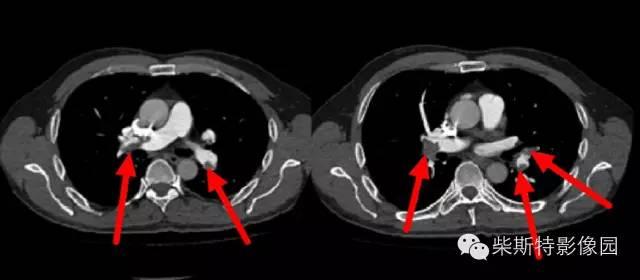

第二大名捕:肺动脉CTA

红色箭头所指处即栓塞导致的充盈缺损,从横断位、冠状位、矢状位三个层面观察,造影剂为高密度白色,而栓子的存在导致造影剂无法充填,从而表现为黑色的低密度影。俗话说的好:长江后浪推前浪!肺动脉CTA的本领已经基本超越其“大哥”肺动脉造影!还可以估测房室大小!